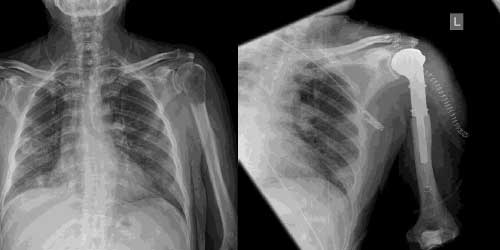

Omurga metastazı, kanserin ilk olarak iç organlarda gelişip daha sonra omurga kemiklerine yayılması sonucu oluşan bir durumdur. Çoğunlukla kan yoluyla sıçrayan bu tür metastaz, hastalarda sırt ve bel ağrısı gibi şikayetlerle kendini gösterir. Erken teşhis ve uygun tedavi yöntemleri, hastaların yaşam kalitesini artırmada kritik bir rol oynar.

Tedavide başarıyı artıran en önemli etkenlerden biri ameliyat öncesi iyi bir hazırlık ve cerrahi planlama yapmaktır. Her şeyden önce tanı doğru konmalı. Bunun için hasta iyi dinlenip, detaylı muayene edildikten sonra tetkikleri dikkatli incelenmelidir.

Her ameliyatın olduğu gibi kemik ve yumuşak doku tümör ameliyatlarının da riskleri vardır. Bu riskleri genel ve yapılan ameliyata özgü olmak üzere kabaca iki başlık halinde gruplandırabiliriz. Öncelikle anestezi ile ilgili risklerin anestezi uzmanı tarafından (...)

Ameliyat sonrası takip ve kontrol hastanın ameliyat masasında uyanması ile başlar. Özellikle damar ve veya siniri ilgilendiren ameliyatlarda hasta ameliyat masasından alınmadan ekstremitenin dolaşımı ve ilgili sinirin fonksiyonu kontrol edilir.